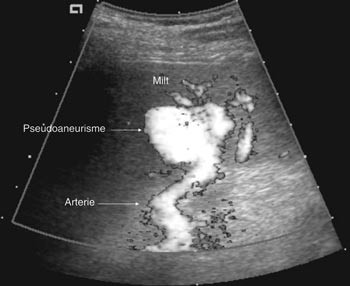

Pasient 2. En 20 år gammel mann ble utsatt for en trafikkulykke. Han var komatøs og ble intubert på skadestedet. CT-undersøkelse ved Ullevål universitetssykehus viste venstresidig pneumothorax og costafrakturer. I milten forelå en laserasjon kaudalt (skadegrad III), men normale funn i hilusnivå (e-fig 4). Pasienten ble observert og overflyttet til lokalsykehus etter tre dager. Seks dager etter traumet ble det gjort en CT-kontroll med arteriell kontrastfase. Denne viste en tilkommet, høytattenuerende lesjon ved milthilus, forenlig med et pseudoaneurisme (e-fig 5). Pasienten ble flyttet tilbake til Ullevål universitetssykehus hvor det ble utført angiografi med embolisering (e-fig 6). Ultralydkontroll samme dag viste opphørt sirkulasjon i lesjonen. Tre dager senere ble pasienten utskrevet.

I litteraturen er det beskrevet redusert sensitivitet og spesifisitet for pseudoaneurismer ved CT-undersøkelse sammenholdt med angiografi (8), men undersøkelsene er som oftest kun gjort i venøs kontrastfase. I flere studier er det benyttet forsinkelse fra kontrastinjeksjon til bildeopptak på mellom 70 og 85 sekunder som tilsvarer sen eller venøs kontrastfase (1, 9, 10). CT-bildene fra undersøkelsen av pasient 1 illustrerer at dette kan vanskeliggjøre diagnostikken. I tillegg er det viktig å vite at vaskulære lesjoner kan presentere seg forsinket. Det viser bildene av pasient 2. CT-undersøkelse i arteriell og venøs fase etter 5 – 7 dager i tillegg til undersøkelse ved innkomst er derfor anbefalt (2, 6).